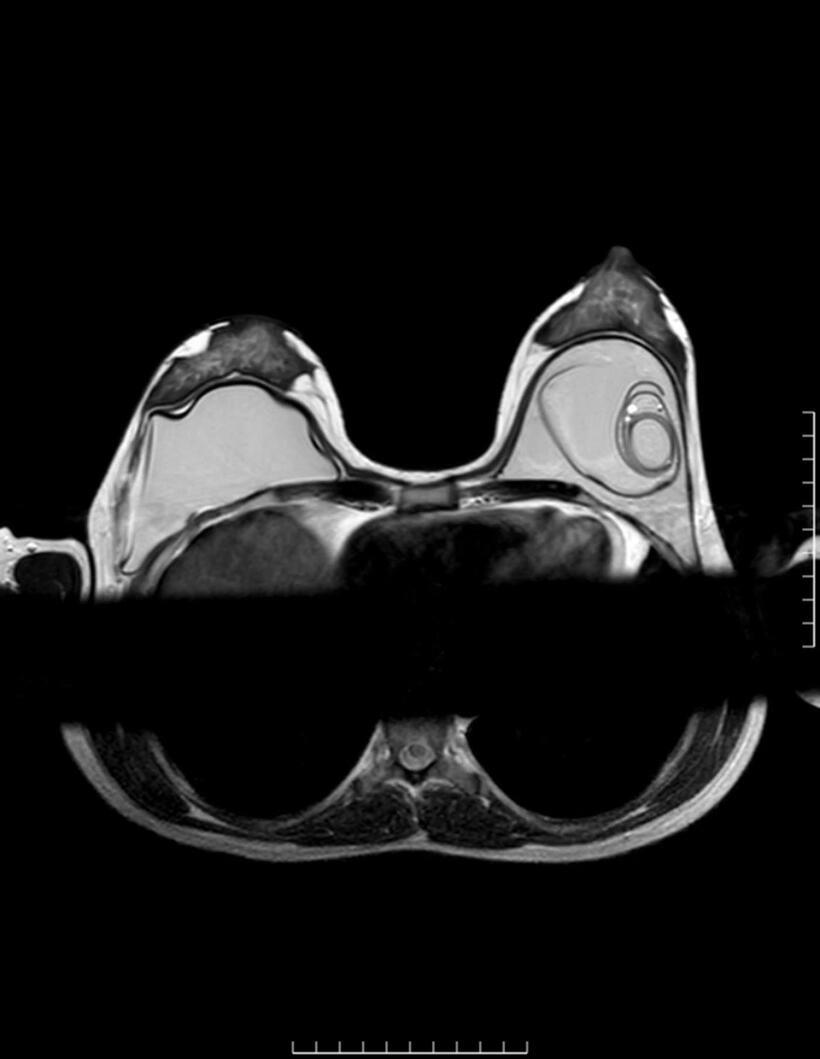

Hình ảnh CT vỡ túi ngực.Ảnh: BSCC

Vỡ túi ngực là tình trạng lớp vỏ implant bị rách hoặc nứt, làm chất bên trong thoát ra ngoài. Với túi nước muối, biểu hiện thường rõ rệt khi ngực xẹp nhanh. Trong khi đó, với túi silicone gel – đặc biệt là loại gel kết dính – silicone có thể vẫn nằm trong bao xơ, khiến hình dạng ngực không thay đổi đáng kể. Đây là lý do nhiều trường hợp được gọi là “vỡ túi thầm lặng”.

ThS.BS Nguyễn Minh Nghĩa khuyến cáo, người đã nâng ngực cần duy trì thăm khám định kỳ để phát hiện sớm các bất thường. Việc theo dõi nên kết hợp khám lâm sàng và các phương pháp chẩn đoán hình ảnh như siêu âm hoặc cộng hưởng từ (MRI).